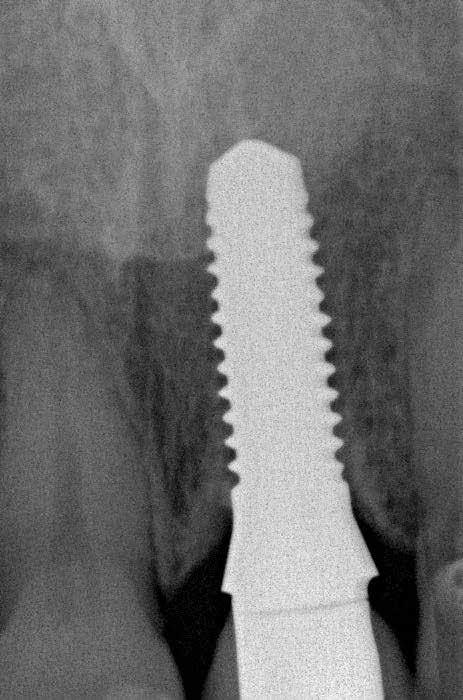

Az implantátumágy előkészítéséhez a fúrást a fogmeder palatinális oldalán végeztük (7. ábra), hogy megőrizzük a bukkális csontot és elkerüljük, hogy túl nagy nyomás legyen rajta az implantátum behelyezésekor� Miután az implantátum helyét kialakítottuk a megfelelő sebészi szettel, az implantátumot 40 Ncm-es behelyezési nyomatékkal helyeztük be (8. ábra)�

gömbfúróval, majd 2 mm-es előfúróval 13 mm-ig fúrtam� Amint az előfúrás sikeres, már nem nehéz tovább tágítani egészen 4,5 mm-ig [7]� Az implantátum ágyát ellenőriztük a megfelelő eszközzel, majd dezinfektáltuk ózonnal� Az implantátumot be lehet helyezni kézzel, racsni segítségével, vagy a megfelelő gépi behajtóval� Ennél az esetnél a primer stabilitást 40 Ncm-es behelyezési nyomatékkal sikerült elérni (9. ábra)� Kontrollröntgent (10. ábra) és egy üvegszálas csapot készítettünk a szék mellett extraorálisan� Egy dummy implantátumot használtunk, hogy könynyebb legyen az elkészítése (11. ábra)� A bepróbálás után az üvegszálas csapot RelyX Unicem-mel ragasztottuk be, az ideiglenes koronát szintén a rendelőben készítettük el a szilikonkulcs segítségével [8]� Az üvegszálas csapot vazelinnel izoláltuk és a koronát ideiglenes ragasztóval ragasztottuk, hogy el tudjuk távolítani a későbbiekben (12. ábra)� A kontrollröntgeneken (13. ábra) a csont jól megtartottnak tűnt, és az ideiglenes koronát át lehetett adni (14. ábra)� A korona sem okkluzióban sem artikulációban nem érintkezett az antagonista fogazattal� Egy nappal (15. ábra) és két héttel (16. ábra) később a lágyszövet szépen gyógyult�